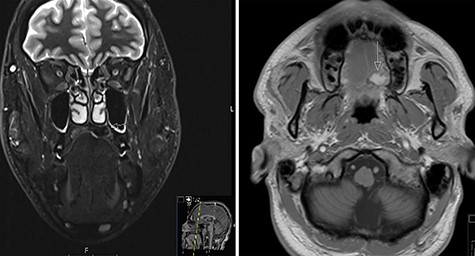

A 37-year-old patient with a recurrent, histologically confirmed steatocystoma of the palate was referred to our clinic. The patient’s medical history had already included two local removals of the tumor. Clinically, in the transition from hard to the soft palate, an asymptomatic, about 1 cm large, round, circumscribed and soft lesion was seen (Fig. 1). Magnetic resonance imaging was performed for further diagnosis and for assessment of spread and tissue infiltration of the finding. Here, a submucosal, 8 × 10 × 8 mm large tumor of delimited growth could be verified. It was T1 hypertense, T2 inhomogeneous partly hypointense, partly isointense with a significant signal drop in the T2 fat saturation (Fig. 2). There was no evidence of bony infiltration. The lesion was resected with a safety margin of 1–2 mm protecting the nerve and the greater palatine artery up to the palatal bone (Figs 3 and 4). As a secondary granulation of the defect was intended, the wound was first treated with a cellulose tamponade and tranexamic acid gel to prevent bleeding. An acrylic splint was then incorporated as a pressure bandage and wound protection (Fig. 5). The histopathological examination of the removed specimen showed a soft and glandular tissue covered with squamous epithelium with manifestations of a cystic, regressively changed epithelial lesion, which was compatible with the clinically known steatocystoma (Fig. 6). Follow-up examinations at 3-month intervals showed a good wound healing with complete restitution without evidence of recurrence after 1.5 years.

MRI scans of steatocystoma simplex involving the left side of the palate